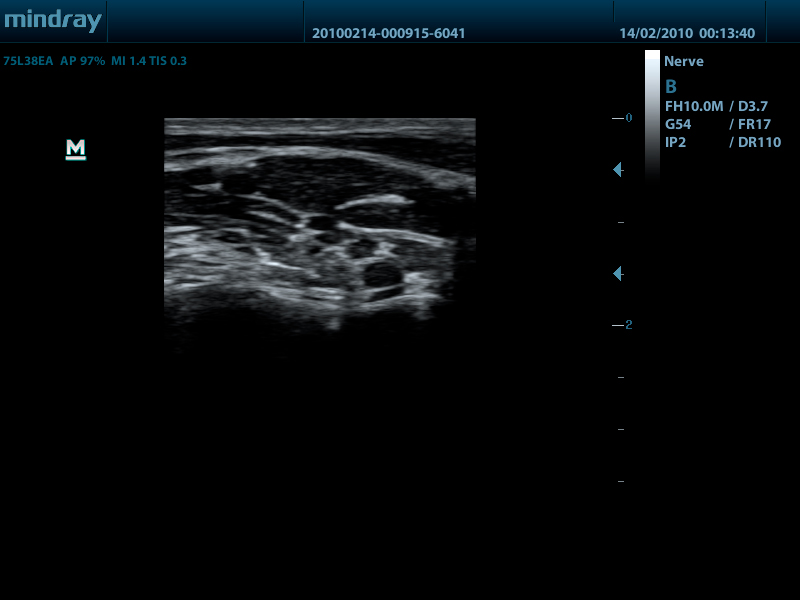

- Широкий выбор мультичастотных датчиков от 2,0 до 14,0 МГц

- Линейный датчик 75L38EA, 3.3 - 13.0 МГц, апертура 38 мм